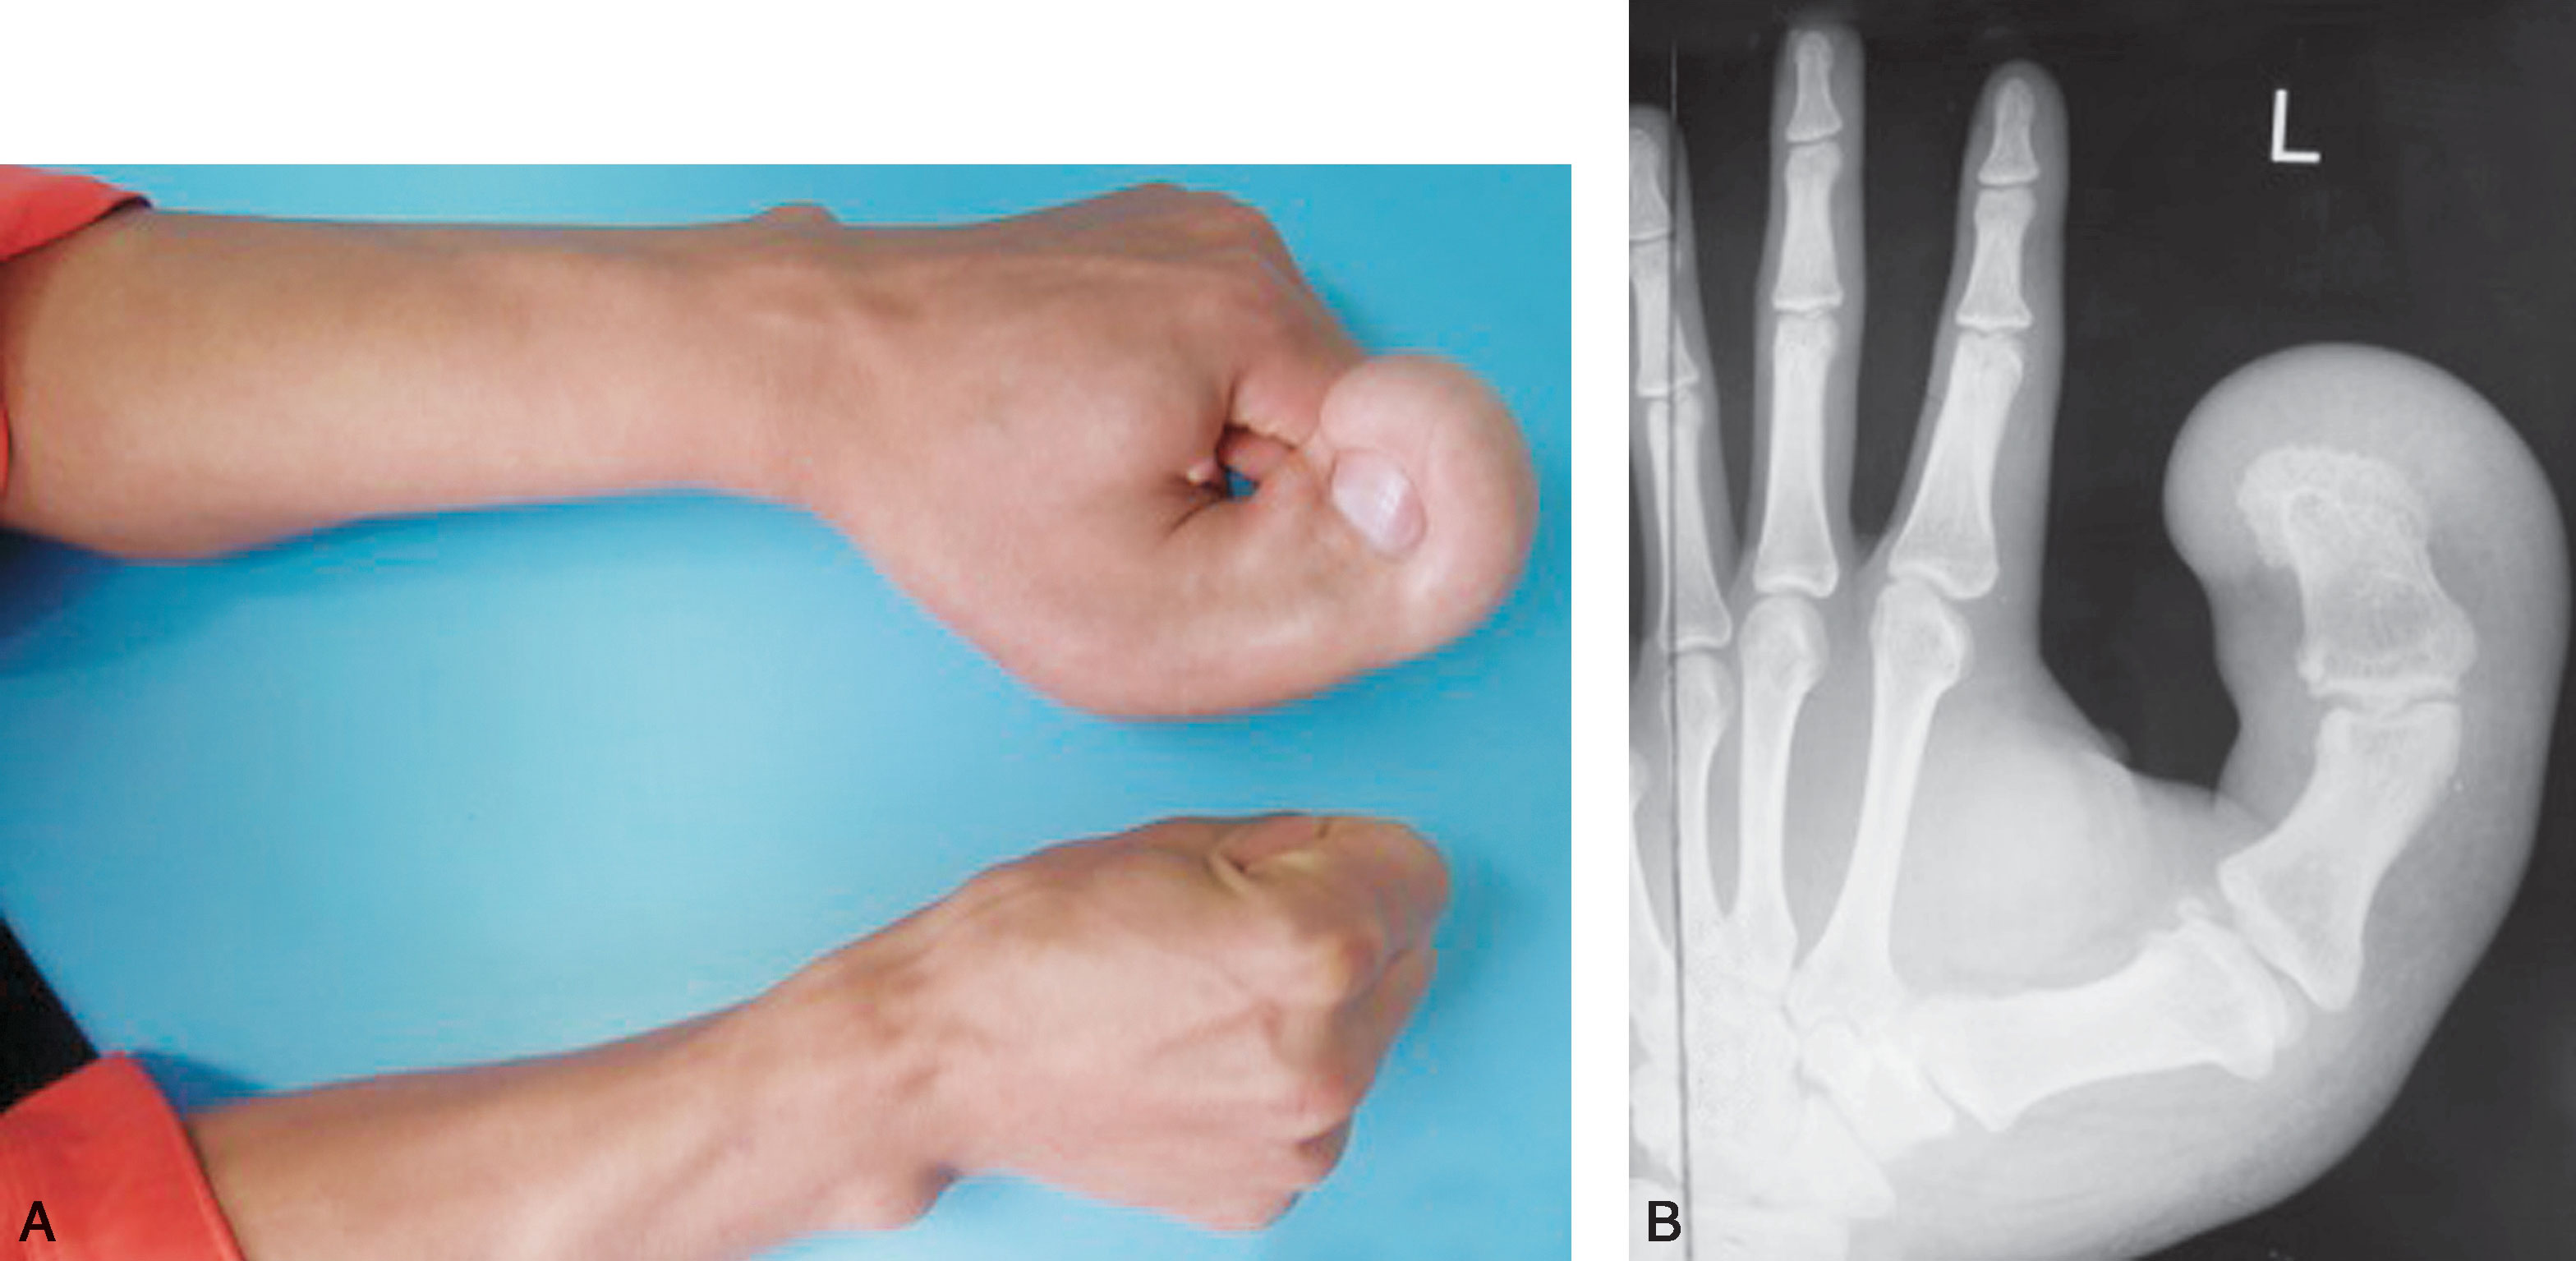

图1-2-29 指间关节融合

图1-2-30 指间关节融合X 线片

先天性双手指间、掌指关节纤维性(或软骨融合)融合